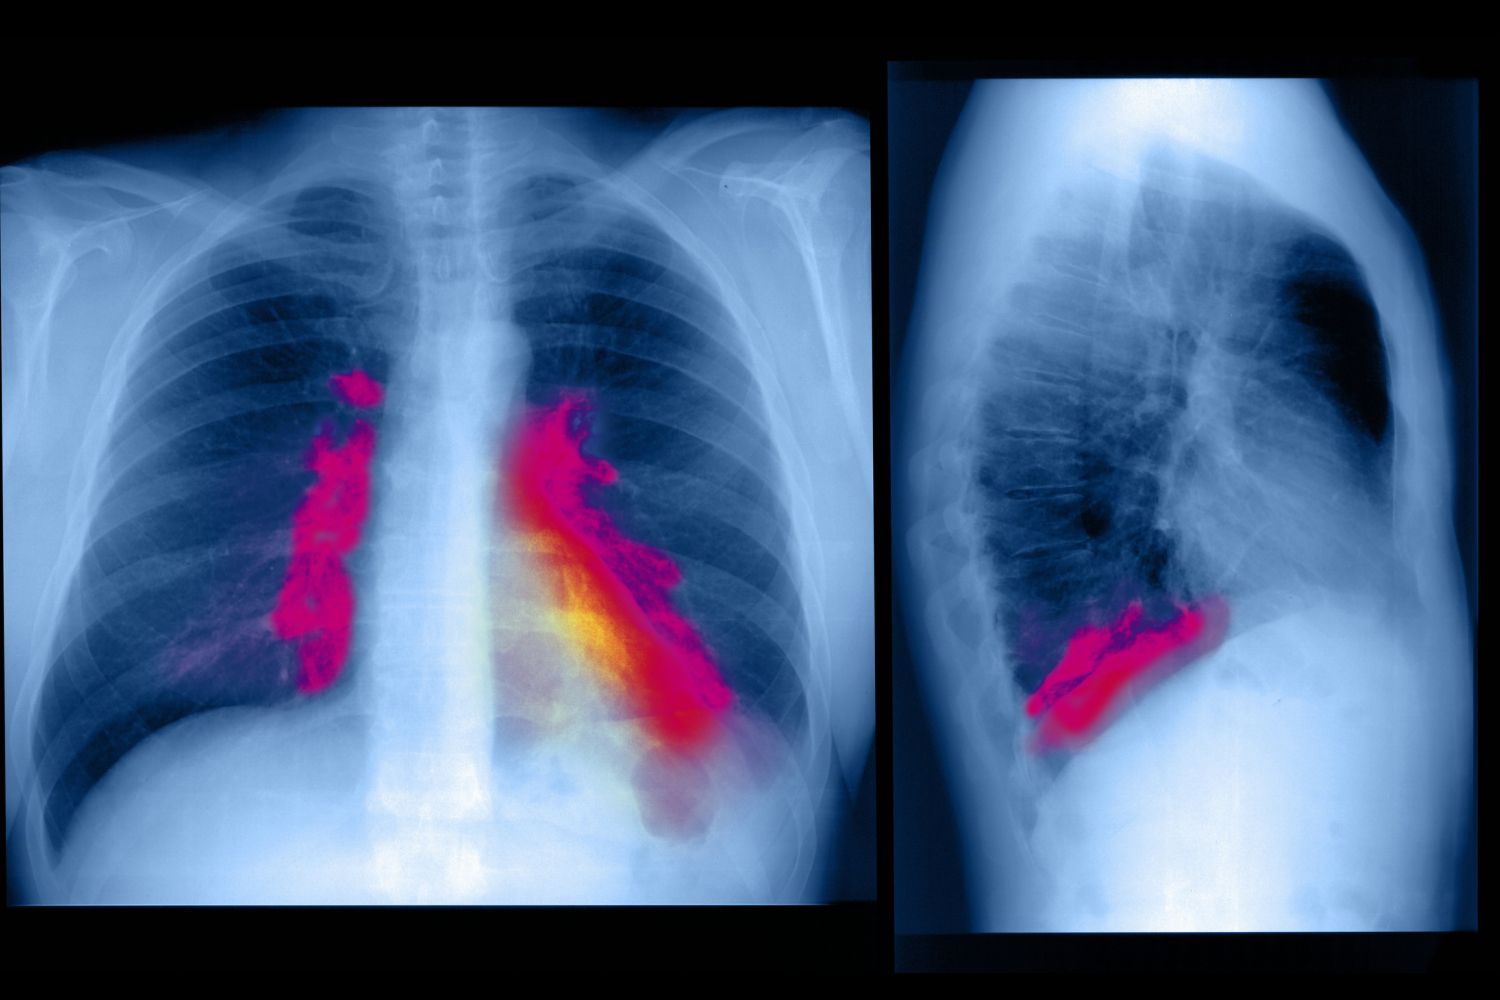

Solunum yapılarının dış ortama maruz kalması nedeniyle solunum sistemi enfeksiyonları yaygındır. Solunum yapıları bazen bakteri ve virüs gibi bulaşıcı ajanlarla temas eder. Bu mikroplar solunum dokusunu enfekte ederek iltihaplanmaya neden olur ve üst solunum yolunun yanı sıra alt solunum yolunu da etkileyebilir.

Alt solunum yolu enfeksiyonları genellikle üst solunum yolu enfeksiyonlarından çok daha tehlikelidir. Alt solunum yolu yapıları arasında trakea, bronşiyal tüpler ve akciğerler. Bronşit (bronşiyal tüplerin iltihabı), pnömoni (akciğer alveollerinin iltihabı), tüberküloz ve grip, alt solunum yolu enfeksiyonlarının türleridir. Temel Çıkarımlar Solunum sistemi organizmaların nefes almasını sağlar. Bileşenleri bir grup kas, kan damarı ve organdır. Birincil işlevi, karbondioksiti dışarı atarken oksijen sağlamaktır. Solunum sistemi yapıları üç ana kategoriye ayrılabilir: hava yolları, pulmoner damarlar ve solunum kasları. Solunum yapılarının örnekleri arasında burun, ağız, akciğerler ve diyafram yer alır. Solunum sürecinde hava akciğerlere girer ve çıkar. Gazlar hava ve kan arasında değiş tokuş edilir. Gazlar ayrıca kan ve vücut hücreleri arasında değiş tokuş edilir. Solunum sisteminin değişen ihtiyaçlara uyum sağlaması gerektiğinden, solunumun tüm yönleri sıkı kontrol altındadır. Solunum sistemi enfeksiyonları, bileşen yapıları çevreye maruz kaldığından yaygın olabilir. Bakteriler ve virüsler solunum sistemine bulaşabilir ve hastalığa neden olabilir.